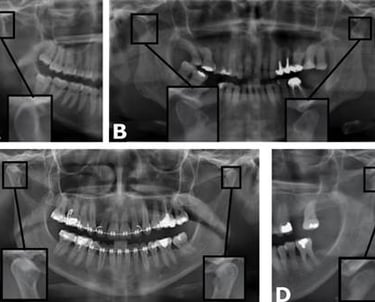

Se utilizan radiografías para visualizar la estructura ósea de la ATM, identificar problemas estructurales y evaluar la salud de la articulación.

Evaluación radiográfica de la articulación temporomandibular (ATM)